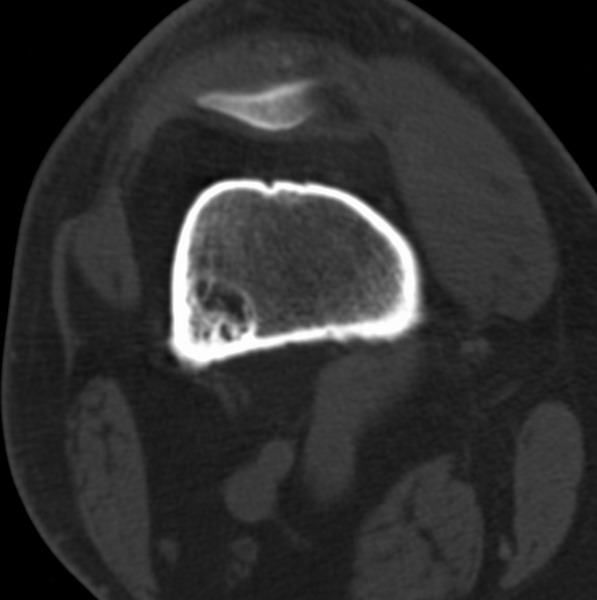

右侧膝关节疼痛一月

男、48

股骨下段、胫骨上段。

1、股骨干骺端病变考虑干骺端纤维性皮质缺损愈后(非骨化性纤维瘤)改变,胫骨近端内生骨瘤(或干骺端纤维性皮质缺损愈后改变);

2、骨关节炎,骨质增生,股骨外侧髁退变性囊肿(关节面软骨下囊肿);

1、股骨干骺端病变考虑干骺端纤维性皮质缺损愈后(非骨化性纤维瘤)改变,胫骨近端内生骨瘤;